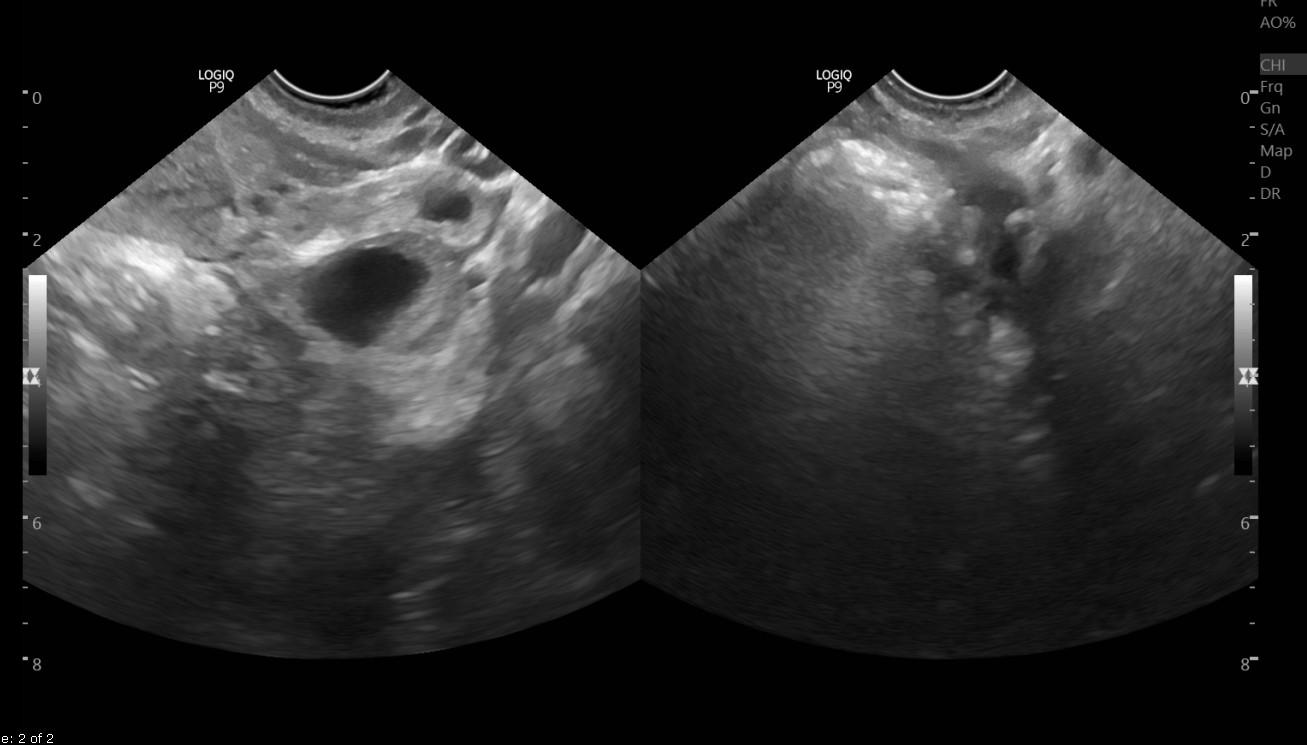

Mang thai tại vết mổ đẻ cũ là hiện tượng thai làm tổ tại vị trí vết mổ đẻ cũ. Thời gian gần đây, khi tình trạng mổ lấy thai gia tăng thì hiện tượng này cũng ngày càng gia tăng theo. Đây là một biến chứng thai sản rất nguy hiểm. Đối với những thai phụ đã sinh mổ một hoặc nhiều lần trước đó, trong lần mang thai này có chẩn đoán chửa tại vết mổ cũ thì cần được điều trị ngay. Nếu càng để lâu, kích thước bào thai càng lớn thì nguy cơ gây tai biến cho người bệnh càng nghiêm trọng hơn như: rau cài răng lược, băng huyết, vỡ tử cung, phải cắt bỏ tử cung, thậm chí gây nguy hiểm đến tính mạng người bệnh.